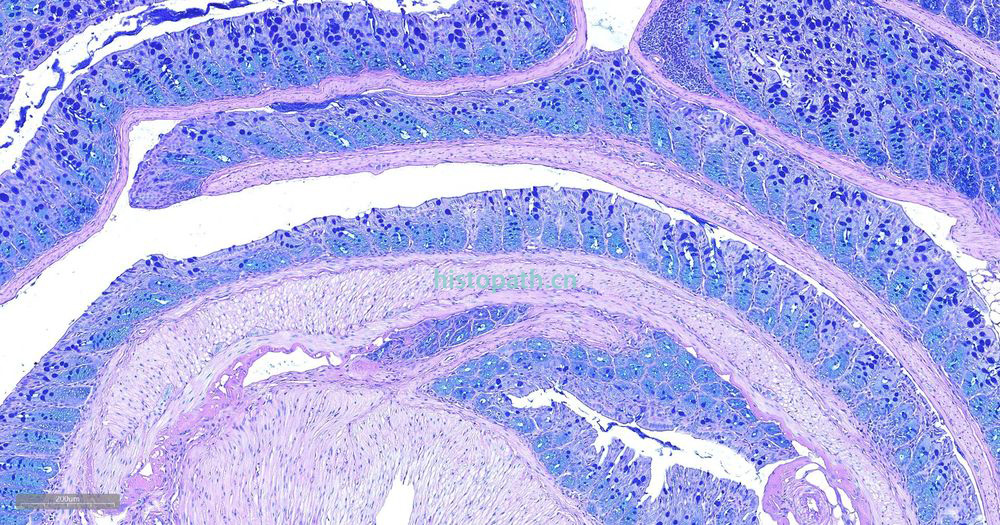

糖原染色是病理学中常规的染色方法之一,该法常用来显示糖原和其他多糖,该染色液不仅能够显示糖原,还能显示中性黏液性物质和某些酸性物质。

阿利新蓝和PAS技术联合使用可鉴别同一组织切片中的中性黏蛋白和酸性黏蛋白。这种技术也常用作广泛检测黏蛋白的手段。阿利新蓝可将唾液黏蛋白、硫黏蛋白和蛋白多糖染成蓝色。PAS技术可将中性黏蛋白染成深红/红紫色,同时将既含中性黏蛋白有含酸性黏蛋白的组织和细胞染成深浅不同的紫色,这是由于阿利新蓝与 Schiff试剂结合并反应。上述染色常可出现在含有中性黏蛋白和唾液黏蛋白的小肠杯状细胞中。

阿利新蓝是类铜钛花青染料,这种阳离子染料与酸性基团结合,也即阿利新蓝与组织内含有的阴离子基团如羧基和硫酸根形成不溶性复合物。分子中带正电荷的盐键与酸性黏蛋白多糖物质中带负电荷的酸性基团结合形成不溶性的复合物而呈蓝色,再与PAS进行复合染色,就能显示三种不同黏液物质成分。

染色结果: